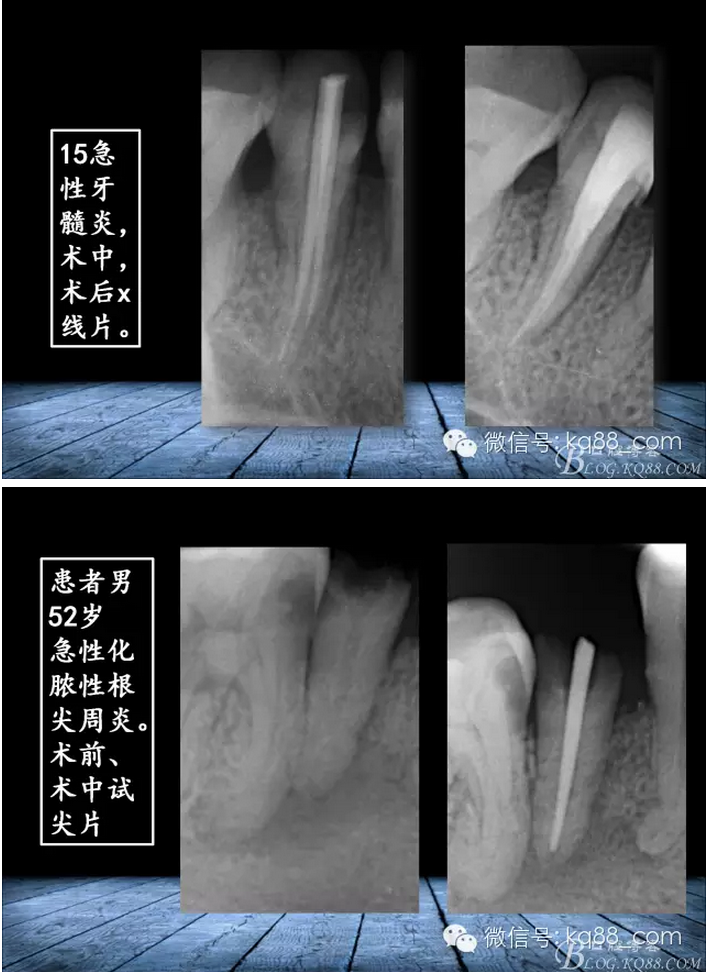

張瑞鋒:簡(jiǎn)單的事情認(rèn)真做——我的根管治療